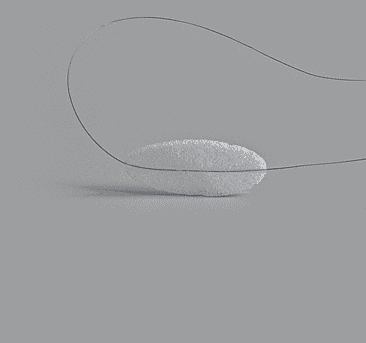

Lower Eyelid Implant